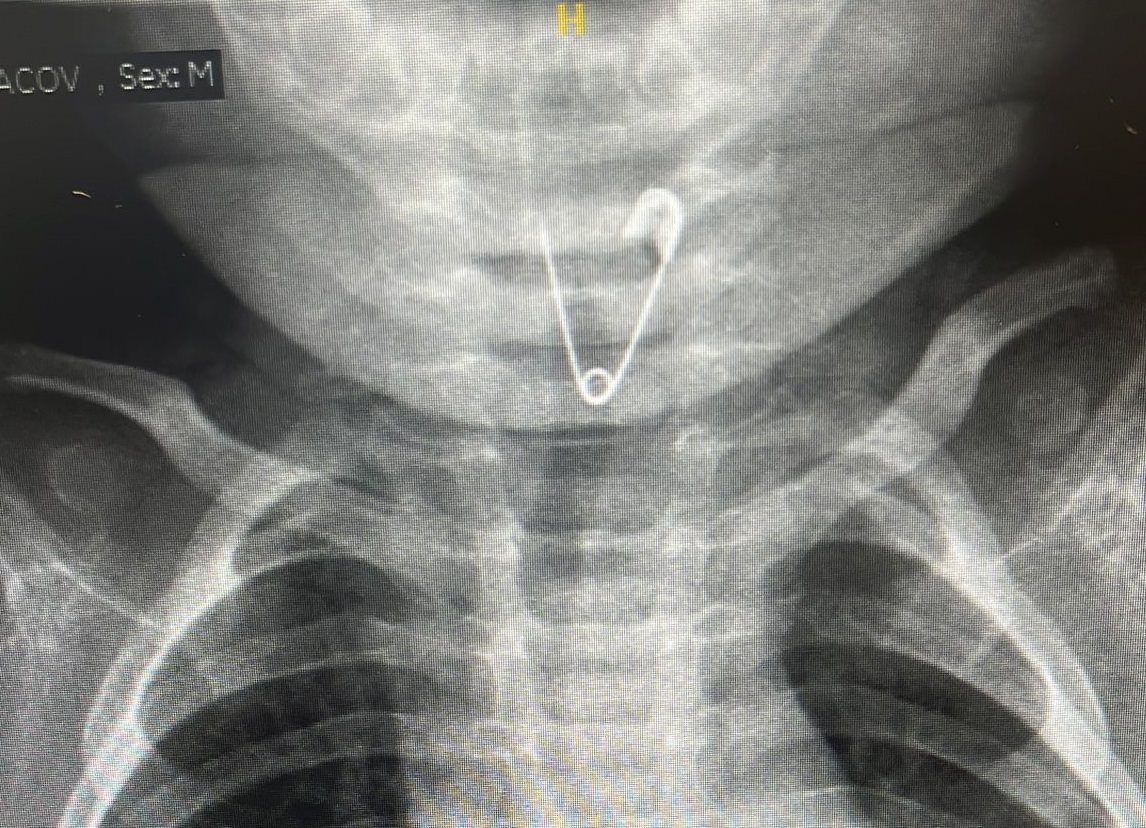

חייו של תינוק בן 9 חודשים ניצלו בזכות ניתוח חירום בבית החולים אסותא באשדוד. התינוק בלע סיכת ביטחון, הוריו הבהילו אותו לבית החולים במהירות, ובצילום נצפתה סיכת ביטחון פתוחה בוושט התינוק

עם קבלתם במלר"ד ילדים הם טופלו ע"י ד"ר הגר גור סופרמן מנהלת המלר"ד. למרות מצבו המצוין בבדיקה הוא נשלח מיד לצילום רנטגן בו נצפתה סיכת בטחון פתוחה בכניסה לוושט. התינוק נשלח במהירות לחדר הניתוח שם נותח ע"י רופאים ממחלקת אף אוזן גרון, ד"ר שוורץ וד"ר ירדן תחת הרדמה מלאה שבוצעה ע"י ד"ר מיכה שמיר.

ד"ר הגר גור מנהלת מלר"ד ילדים: "בשעות הצהריים הובא למיון תינוק בן 8 חודשים אשר האב חשד שהכניס משהו לפיו כיוון שראה תנועות אי נוחות סביב הפה. במישוש בבית חשו בגוף זר ואף נצפה דימום קל. הובא אלינו במצב מצוין אולם לאור הסיפור המחשיד בוצע צילום, אשר להפתעת כולם הדגים סיכת ביטחון פתוחה ממוקמת בוושט העליון. מדובר במצב מסוכן בו עלול להיווצר חור על ידי הסיכה בוושט, לגרום לפציעה ודליפת חומצה לחזה ואף סכנת חיים".

למיון הוזעקו צוות אאג - ד"ר ירדן מתמחה וד"ר שוורץ מומחה אא"ג ילדים אשר הבהילו את התינוק לחדר ניתוח. בחדר ניתוח תחת הרדמה מלאה שבוצעה עי ד"ר מיכה שמיר הוצאה הסיכה בבטחה.